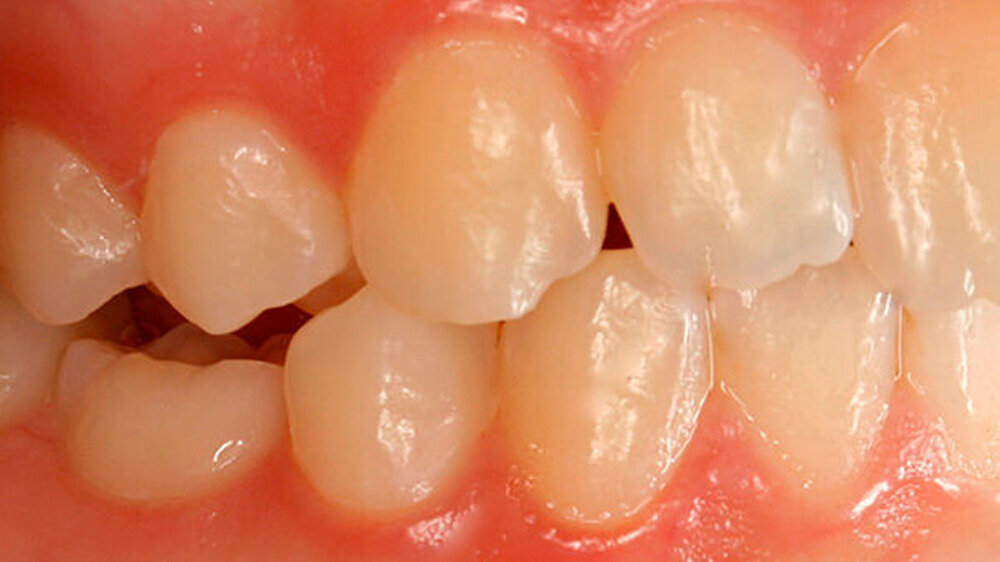

Die Patientin zeigte ein kariesfreies bleibendes Gebiss mit Nichtanlage des Zahns 35 und Persistenz des Zahns 75 auf (Abbildung 1). Sie wies im Frontzahnbereich sowie im rechten Seitenzahnbereich eine Klasse I auf, im linken Seitenzahnbereich aufgrund der Größe des Zahns 75 eine Klasse II. Zahn 75 befand sich in deutlicher Infraokklusion (Abbildung 2). Der Perkussionstest wies allerdings nicht eindeutig auf eine Ankylosierung hin.